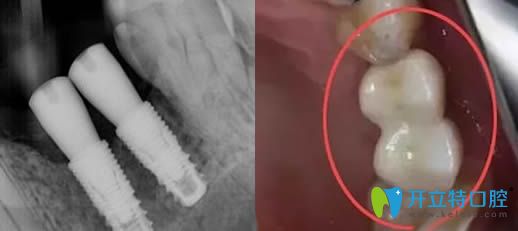

種植體種歪了的效果圖片

所以種植體歪了大家也不要過分擔(dān)心,并不全是種植失敗了。但如果歪斜較重,只能重新種植了,?因?yàn)閮A斜角度過大,則會(huì)造成承受咀嚼的側(cè)向力過大,從而造成種植失敗的。

因此,對于輕微傾斜的植體,在安裝牙冠時(shí),醫(yī)生會(huì)通過角度基臺(tái)來調(diào)整角度,這樣后期牙冠是整齊的,但植體的歪斜是不可逆的。

種植體歪了可以做牙冠調(diào)整修復(fù)